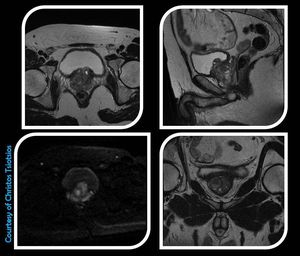

Multiparametric prostate MRI (anatomical and functional). Figure shows three (3) T2-w FSE sequences in all imaging planes and an axial DWI (b0 and b1000). DWI provides information regarding tissue's microarchitecture, and its contribution to prostate MR Imaging is major. Image dataset was acquired at 1.5 Tesla, GE Signa HDxt.